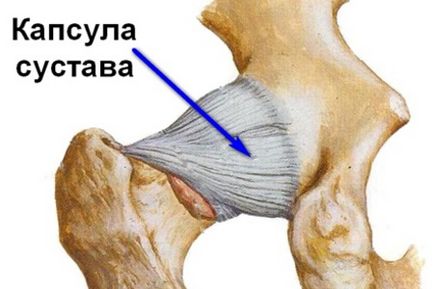

Анатомія тазостегнового суглоба

Зв'язки покликані надійно зафіксувати головку стегна в суглобової западини тазової кістки. Це з'єднання щодня відчуває підвищені навантаження, а значить, має відрізнятися посиленою міцністю. Необхідні властивості забезпечуються внутрішньосуглобових і зовнішніми зв'язками, до яких відносять:

- Поперечну зв'язку суглобової западини.

- Зв'язку голівки стегна.

- Клубово, лобково-, сідничного-стегнові зв'язки.

- Кругову зону.

За рахунок розвиненого зв'язкового апарату суглоб набуває підвищену стійкість до осьовим навантаженням, що необхідно для виконання основних функцій: опори і ходьби.